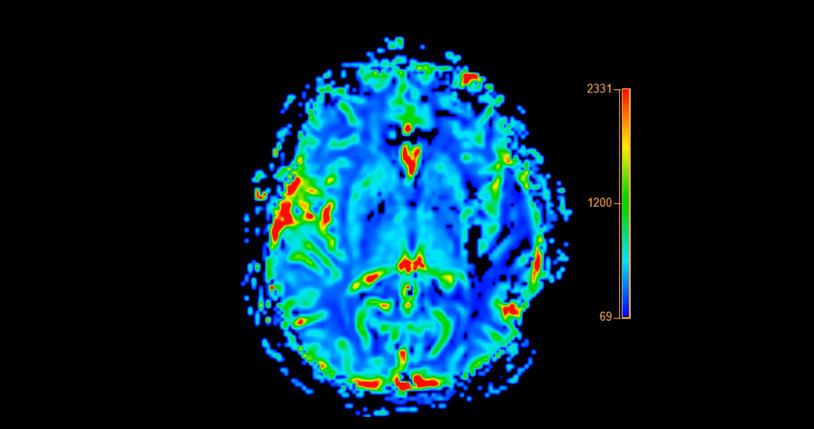

Burada amaç, vücudu ketozis denen metabolik duruma sokmak. Bu durumda vücut enerji için glukoz yerine yağdan üretilen ketonları kullanmaya başlıyor. Alzheimer hastalığında beynin enerji kullanımında ciddi bir sorun yaşanıyor.

Sağlıklı bir beyinde temel enerji kaynağı glukozdur. Ancak Alzheimer hastalığında beynin glukozu kullanma kapasitesi azalır. Nöronlar adeta aç kalır. Bu noktada keton cisimcikleri, beyin için alternatif ve daha kolay kullanılabilen bir yakıt haline geliyor.

Araştırmalara göre ketojenik diyet Alzheimer hastalarında tedaviye olumlu etki ediyor. Ketojenik diyet karbonhidratı ciddi biçimde kısıtlayıp yağdan zengin bir beslenme modeli sunarak vücudu keton üretimine yönlendiriyor. Böylece beyin, glukoz yerine ketonları enerji kaynağı olarak kullanabiliyor. Yani beynin aç kalan hücrelerine alternatif bir enerji kapısı açılıyor.